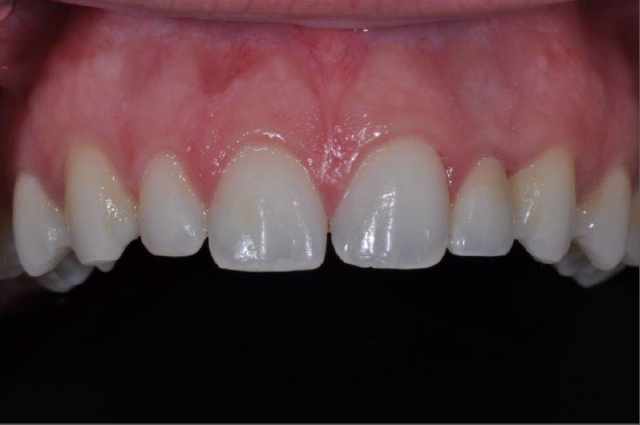

One of the most significant factors of immediate placement is that it decreases treatment time. The healing process of implant therapy is definitive. Depending on all the biologic factors discussed previously, osseointegration occurs slowly. Our patients do not always understand this concept and are not as willing to accept this delay. Patient education is a key factor. Immediate loading certainly increases patient acceptance. Immediate placement of implants at the time of tooth removal maintains optimal soft tissue contours and tissue esthetics.

The emergence profile of the tooth root is more easily captured in the immediate provisional contours, thereby supporting the soft tissues ideally. And, in the absence of infection, the bone response(biology) of the immediate placed implant is favorable.

The failed implant was removed. Following the healing of the site, a second implant was placed. Again, a provisional was placed on the new implant at the time of placement. Maintenance and care instructions were provided. This implant healed uneventfully four months before final restoration. Caroline was delighted with this result.